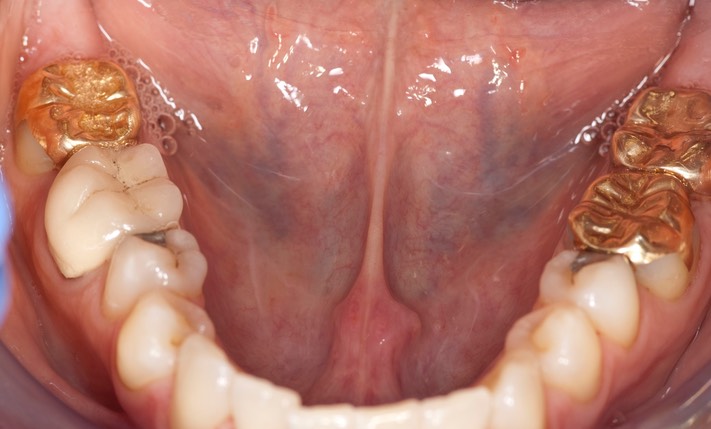

_DSC6212